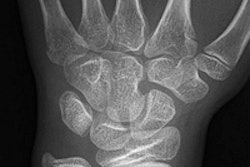

Hamate Fracture

History: A 20-year-old male outfielder who hits left-handed swung and missed the ball. He experienced immediate hypothenar eminence pain. Clinical examination showed tenderness over the muscle belly of the hypothenar eminence in the palm of the hand. No wrist pain or tenderness; demonstrated full range of motion in wrist and fingers. Grip strength was near normal the day after the injury. X-rays, including carpal-tunnel view, were inconclusive for pathology. MRI made the diagnosis of a fracture of the hook of the hamate. Significance: This injury almost always occurs in a hitter who swings and misses and has immediate ulnar palm pain. It is always the bottom hand with which the player holds the bat. This is the significance of this player being a left-handed batter. The bottom hand in the batting position is the right hand in a left-handed batter. The precise mechanism of injury is unclear, but theory has it that the hook of the hamate bangs mechanically against the knob of the bat. Treatment: The San Francisco Giants have found that most if not all such fractures deteriorate to non-union, becoming chronically symptomatic. Therefore, excision of the fractured hook is performed as soon as the diagnosis is made. Return to full competition is usually possible within 6 weeks, although players have returned as early as 3-4 weeks. Image and case study courtesy of the San Francisco Giants and Clinical Diagnostic Radiology, Phoenix. |